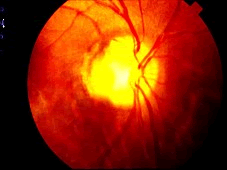

(如图)该种疾病的病因可能是由于()

(如图)该疾病的说法正确的是()